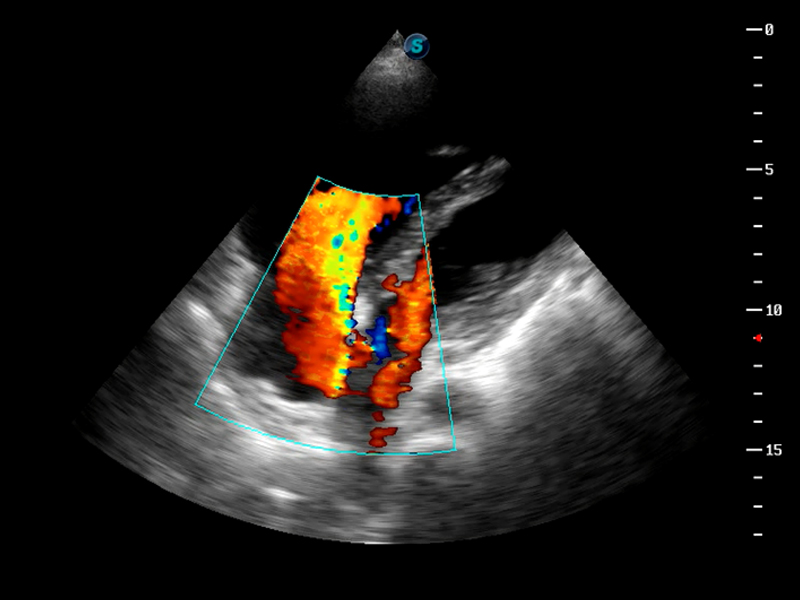

S9便携式彩色多普勒超声诊断仪是米兰官方网站研发的高端便携彩超设备,外观设计新颖、产品性能卓越。S9在便携超声领域采用了突破传统的触摸屏交互设计,并以先进的软件硬件技术和设计理念,为您带来清晰的图像质量、稳定的工作性能和便捷的操作体验。

TDI组织多普勒成像